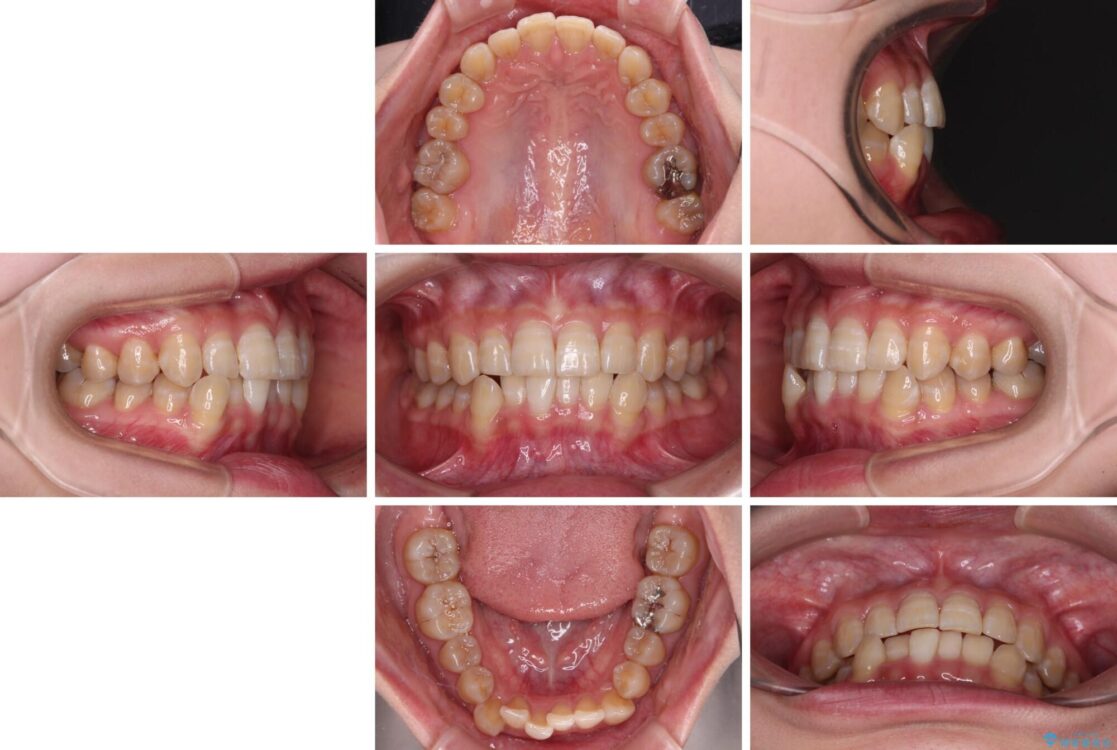

治療後について

治療前、下顎前歯のデコボコが集中しており、奥歯の咬み合わせは、上顎に対して下顎が前方位にある状態でした。下顎の歯列を後方へ移動させる治療はインビザラインの得意とするところですので、1年程度で無事に治療を終えることができました。

治療後

• 【モニター】下顎前歯のデコボコをインビザラインできれいに 治療後画像